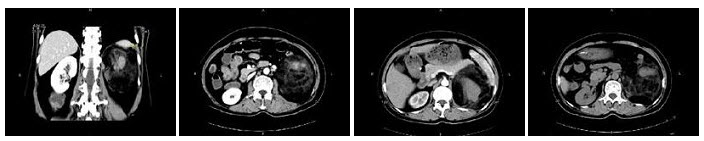

60、多项选择题

女,63岁,突发性肉眼血尿伴下腹胀,无外伤病史,左腰部叩击痛,CT扫描如图示,下列说法正确的是()

A.平扫左肾盂输尿管连接处可见高密度肿块影

B.增强后,肾实质强化明显而病灶处无强化,形成明显对比

C.病灶边缘光滑,清晰

D.考虑为肾盂血块

E.考虑为肾盂输尿管癌